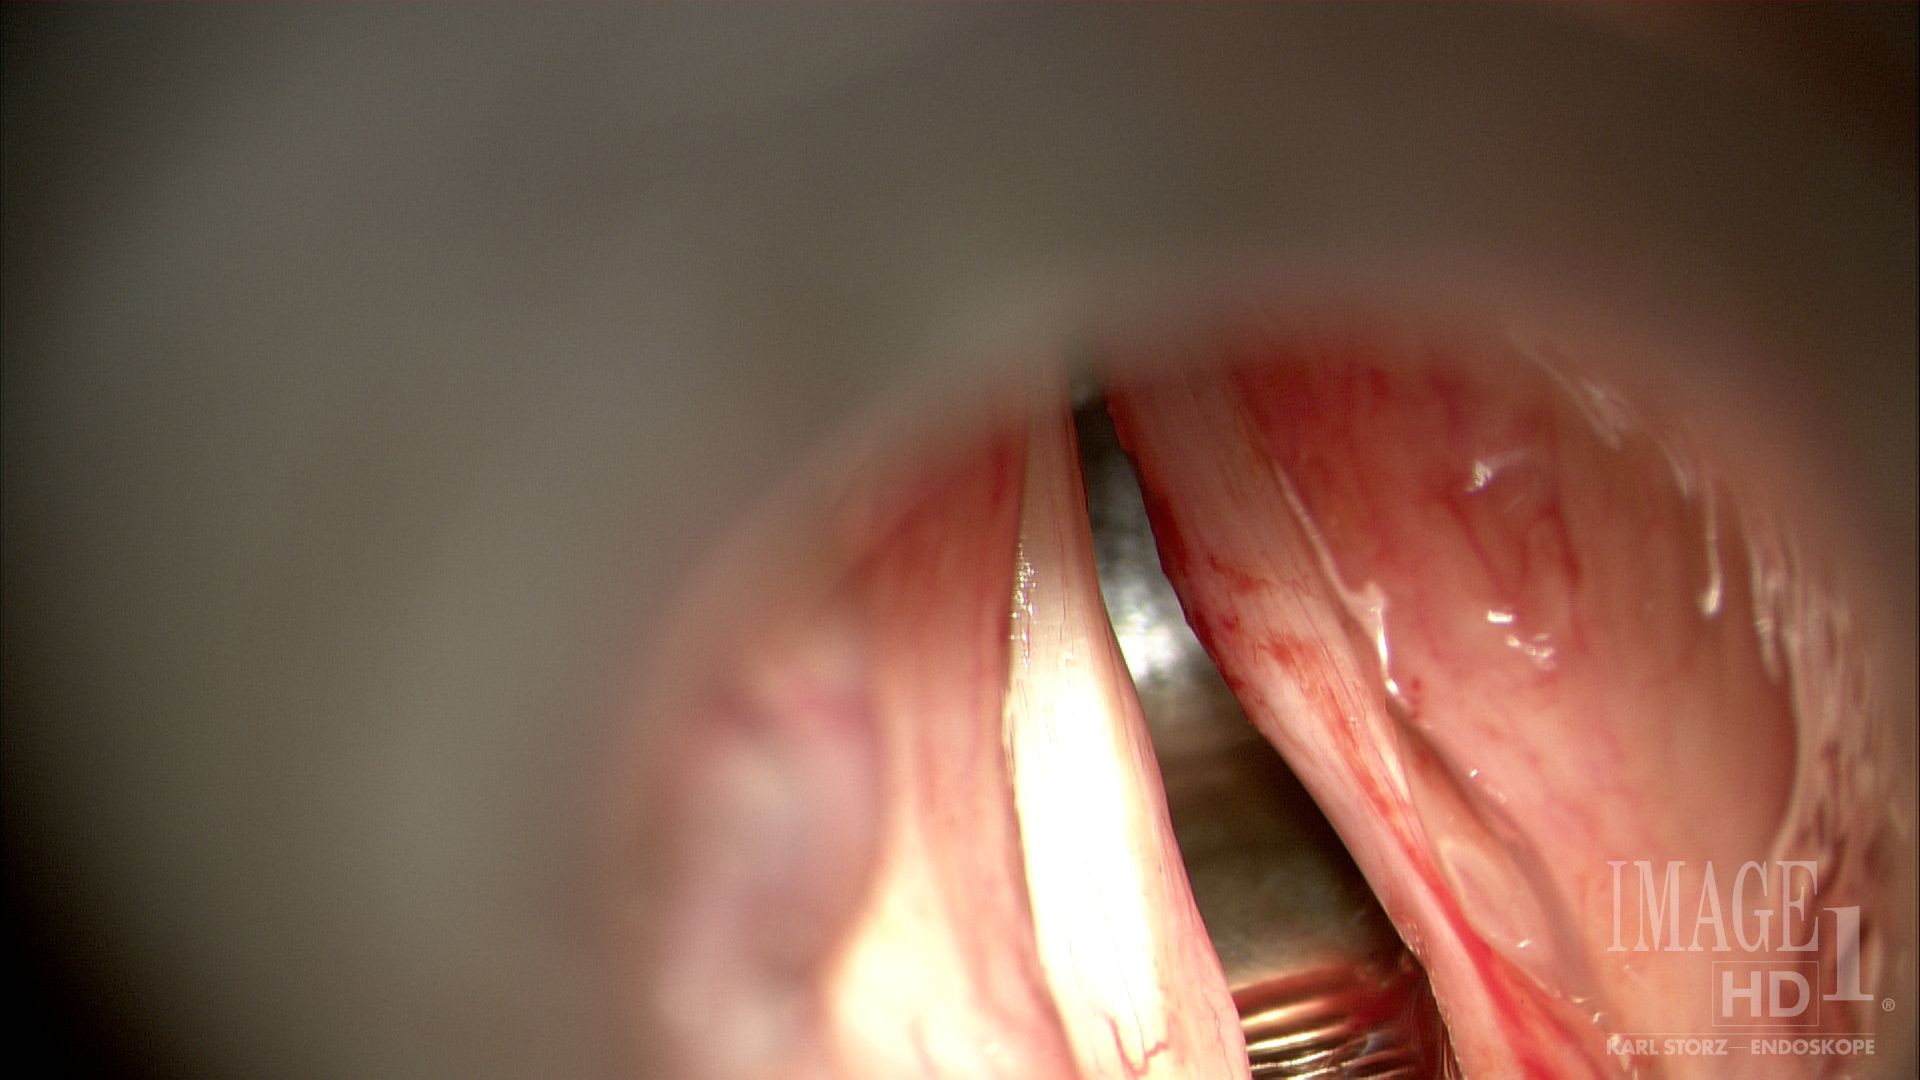

2.03 CO2 laser ex vocal fold lesion POpaps

2.03 CO2 laser ex vocal fold lesion PrePap

After: CO2 Laser Excision of Papilloma